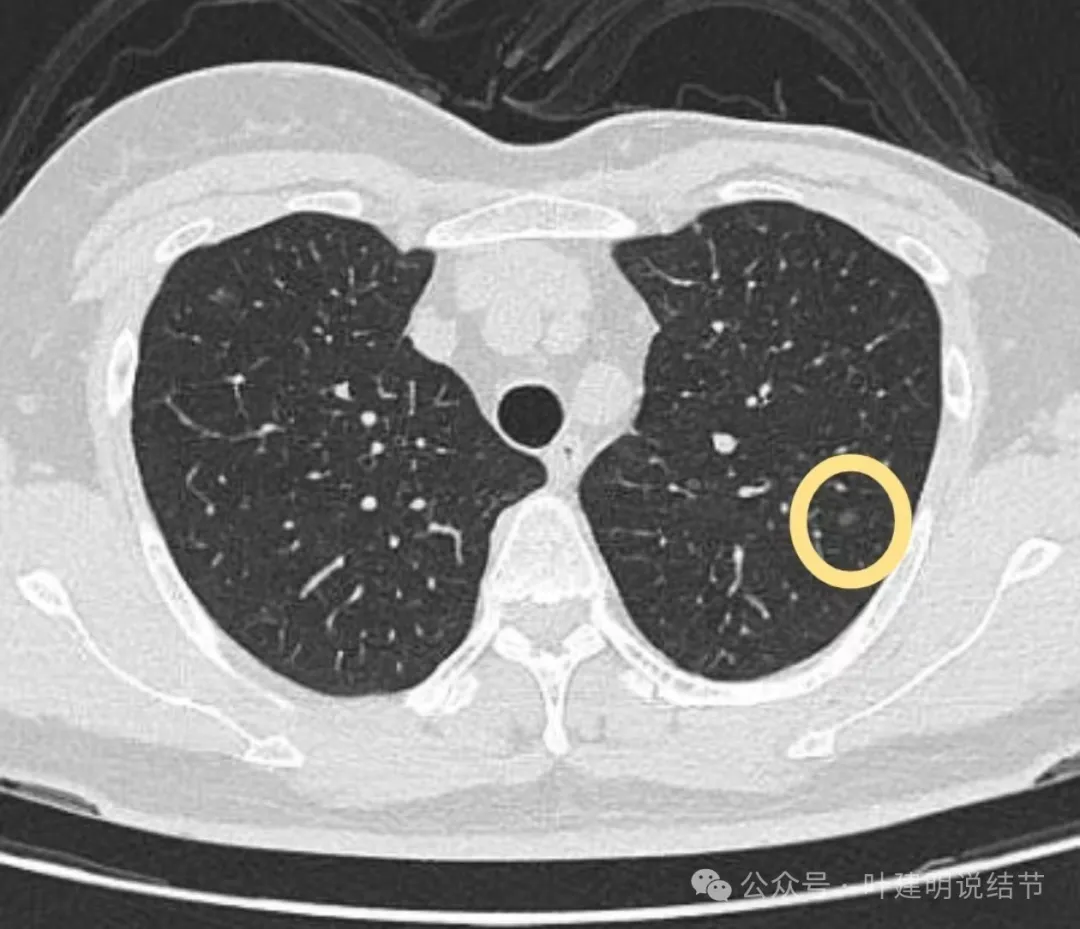

左上叶微小磨玻璃结节,轮廓较清,密度较淡,没有实性成分,考虑肺泡上皮增生或不典型增生可能性大,近期风险小,能随访。

病灶出现,轮廓不清,边缘显糊。

有细支气管通气征,沿扩张的细支气管两侧有密度较高的阴影,再外围有淡的边界不清的磨玻璃成分。

有血管经过病灶处,但距离这么近,血管却没有被影响或形成血管弯。绿色箭头处距病灶有一定距离,但也有淡而模糊的磨玻璃影。

病灶附近多发微小空泡样结构(砖色箭头),病灶边缘轮廓不清(如天蓝色箭头所示),病灶内部有实性密度伴空泡征的结节。

绿色箭头所示的磨玻璃影与主病灶并不相连的;主病灶轮廓不清;附近许多小空泡样结构;血管没有异常增粗或进入病灶内。